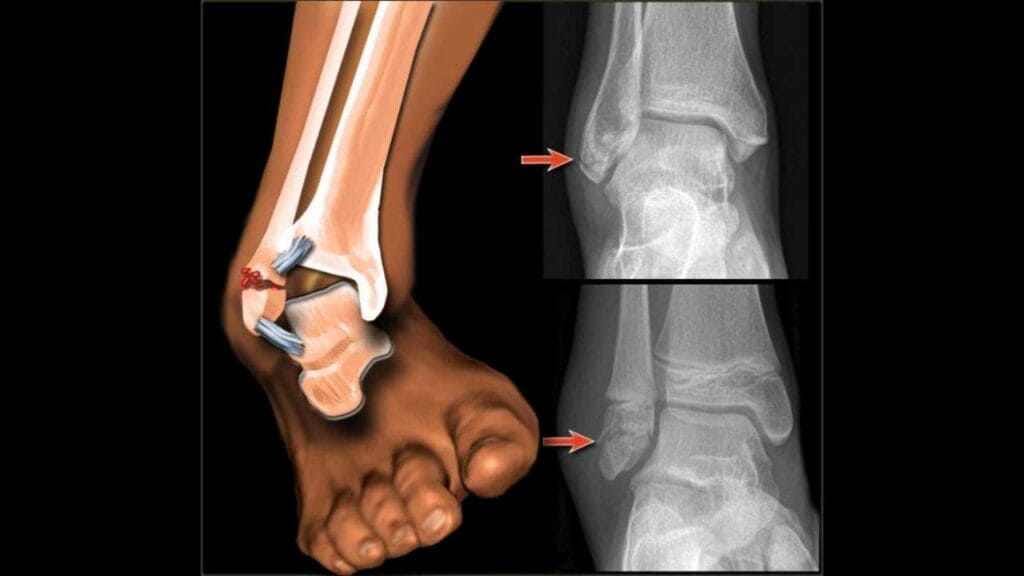

تعرض شاب ينحدر من مدينة بن الطيب، مساء الثلاثاء، لكسر على مستوى الكاحل أثناء ممارسته للرياضة، ليتم نقله على وجه السرعة إلى المستشفى الإقليمي بالدريوش قصد تلقي الإسعافات الضرورية، إلا أن أسرته تفاجأت بإخبارهم بأن الطبيب المختص في جراحة العظام غير متوفر خلال الأيام المقبلة.